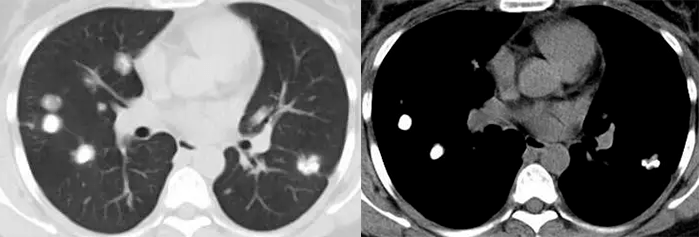

患者的肺部ct检查变化图,结果表明患者肺部肿瘤明显缩小

魏女士治疗前(粉红色圈圈内为肺肿瘤)和治疗后(肿瘤几乎消失)ct图像